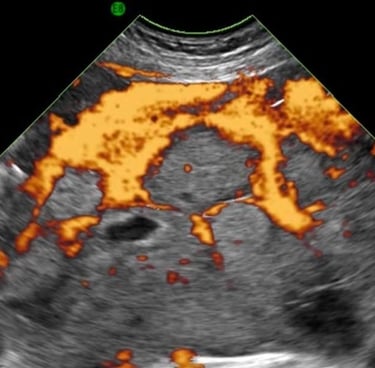

We are revolutionizing tissue perfusion analysis through advanced analysis of 3D sonogram using AI based standalone software

Our technology provides validated and cost-effective quantification of tissue perfusion, without contrast, enhancing diagnostic capabilities in obstetrics, oncology, and nephrology for improved patient outcomes.

We characterize tissue perfusion to give functional insight into tissue in the placenta and kidney and angiogenesis in cancer.